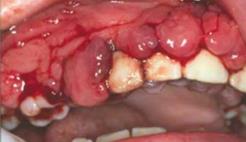

Nem ritka, hogy a leukaemia első tünete a szájnyálkahártyán jelenik meg, igen változatos formában, de elsősorban a gingiván manifesztálódik, mely a leukaemia típusától függően vagy jelentős ínyduzzanat vagy ínyfekély formájában, vagy a kettő kombinációjában manifesztálódik. A duzzadt gingiva soha nem fibroticus, hanem törékeny, hyperaemiás, szivacsszerű és spontán vérzik. A 15.4. táblázat a leukaemiák szájtüneteit mutatja. Néhány esetben a nem túl súlyos ínyhyperplasia az akut myeloid leukaemia első jele, az íny nem hyperplasticus, csak gyulladásmentes mély ínyfekélyek jelennek meg, és az íny spontán vérzik (15.4. ábra (a, b)–15.5. ábra (a, b)).

15.4. ábra. Akut myeloid leukaemia szájtünete a szivacsszerű ínyhyperplasia